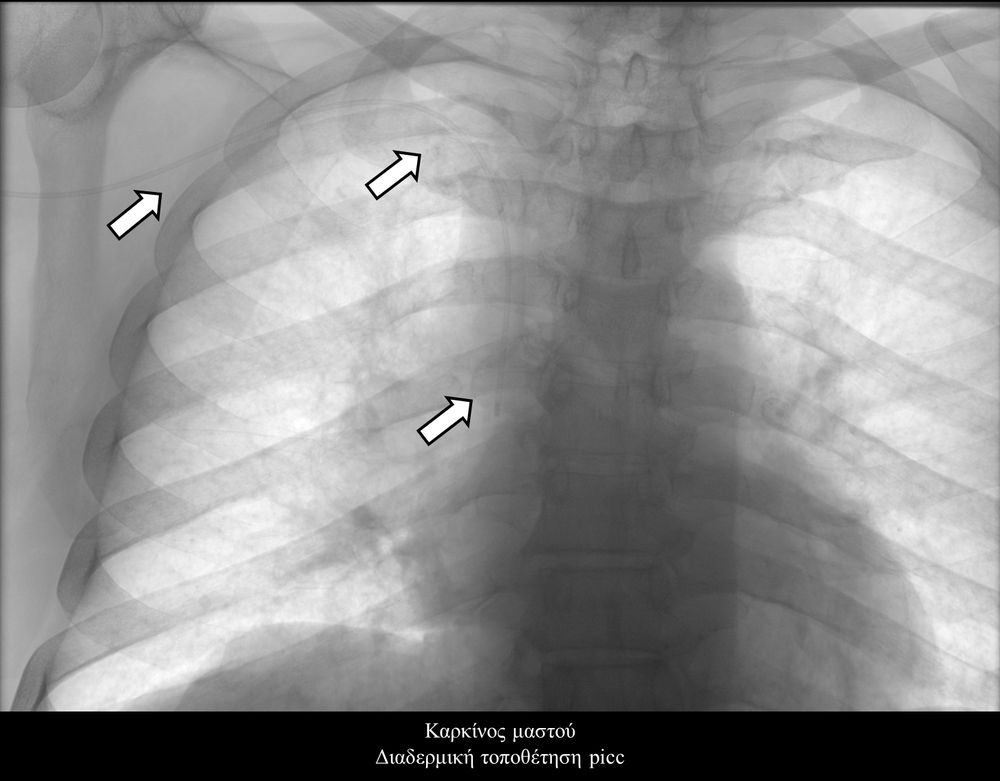

- Οι περιφερικά εισερχόμενοι κεντρικοί καθετήρες (PICC lines) είναι ειδικοί καθετήρες, οι οποίοι εισάγονται από μια περιφερική φλέβα συνήθως των άνω άκρων(π.χ βασιλική ή κεφαλική φλέβα) και προωθούνται μέχρι κεντρικής φλέβας πλησίον της καρδιάς (συνήθως στην άνω κοίλη φλέβα) ώστε να επιτευχθεί η ενδοφλέβια πρόσβαση. Οι καθετήρες PICC μπορούν να χρησιμοποιηθούν για την χορήγηση μιας ποικιλίας φαρμακευτικών θεραπειών ειδικά στον ογκολογικό ασθενή όπως αντιβιοτικών, αναλγητικών, χημειοθεραπείας, παρενετερικής σίτισης ή και για απλή αιμοληψία σε ασθενείς που νοσηλεύονται επί μακρόν στην κλινική ή στην μονάδα εντατικής θεραπείας, καθώς και σε ασθενείς οι οποίοι επιστρέφουν στο σπίτι και επανεισάγονται στην κλινική μόνο για την προκαθορισμένη χημειοθεραπεία τους.